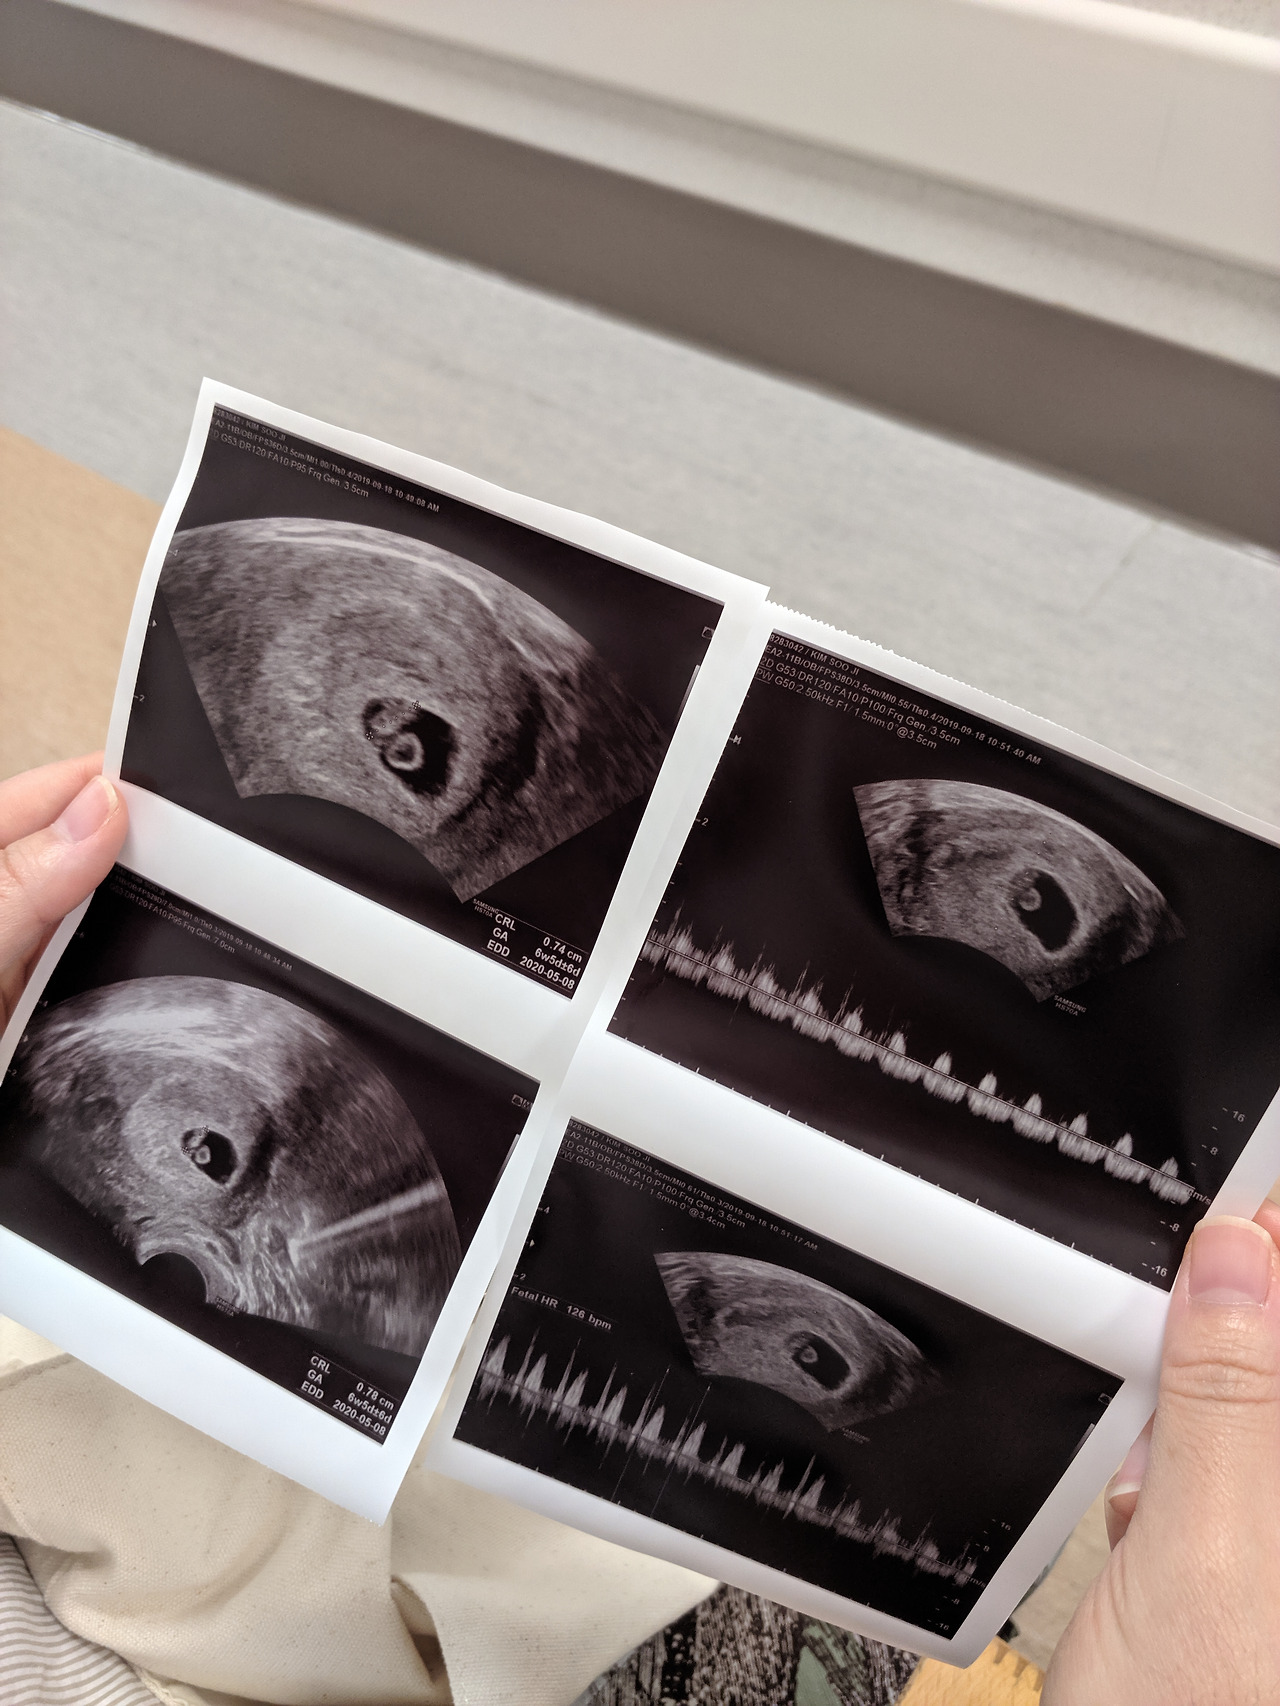

지난주엔 초음파 사진으로 아이의 존재 유무를 확인했다. 이번 주엔 녀석의 심장 뛰는 소리를 들으러 왔다. 지난주에 둘 다 한꺼번에 면 될 것을 왜 병원에 매주 오라고 하는 건지. 그러고 보면 산부인과 의사 선생님들이 사람을 조련할 줄 다. 선 포장을 한 번에 뜯어 모두 보여주지 않고, 하나 조금씩 열어서 보여주니 매번 가슴이 두근두근하 된다. 다음 주엔 과연 어떤 마법 같은 선물로 우리를 기쁘게 해 주실까 기대하 이 마음. 이 분들, 모르긴 몰라도 연애 참 잘하실 것 같다. 밀당에 아주 능숙하시다.

임신부의 심기를 불편하게 할 수 없으니 의사 선생님이 오시기 전까지 아내의 배에서 시선을 돌렸다. 괜히 딴청을 피우면서 천장을 바라보거나 낯설은 기계들을 살피는 척한다. 이제 막 임신해서 배가 나오지도 않았구만 뭐가 그리 부끄러운지. 우리 서로 볼 거 다 본 그렇고 그런 사이인데 별 이상한 지점에서 외하는 아내이다. 검사실에서도 한참을 기다린 끝에 선생님을 맞이할 수 있었다. 사람이 많아서 차례가 한참이나 밀렸단다. 이제는 다시 시선을 돌려 아내의 배를 뚫어져라 바라봤다. 생님은 능숙한 손놀림으로 배에다 젤을 치덕치덕 바르고 마트에서 쓰는 바코드처럼 생긴 기계를 갖다 대고서 이리저리 움직이다가 어느 순간, 우리에게 소리를 들어 보라고 말다.

콩닥 콩닥 콩닥 콩닥 콩닥 콩닥 콩닥 콩닥.

힘차게, 그리고 생각보다 무척 빠른 박자로 뱃속 아이의 심장 뛰는 소리가 들린다. 인생에서 처음으로 경험하는 순간이었다. 하지만 비로소 아버지가 되었음을 실감하는 희의 눈물 같은 건 흐르지 않았다. 대체 언제쯤에야 남들처럼 눈시울을 적시려나. 다른 사람들은 임신테스트기의 두 줄을 확인했을 때, 병원에서 임신 판정을 받았을 때, 초음파 사진을 처음으로 찍었을 때, 뱃속에서 태동이 느껴질 때 등등 많은 순간들에서 감격에 겨워 어쩔 줄 몰라한다던데 나는 아직도 모르겠다.

2019년 9월 18일, 복이의 두근두근거리는 심장소리를 처음으로 들었고 내 가슴도 따라서 두근두근 뛰었다.